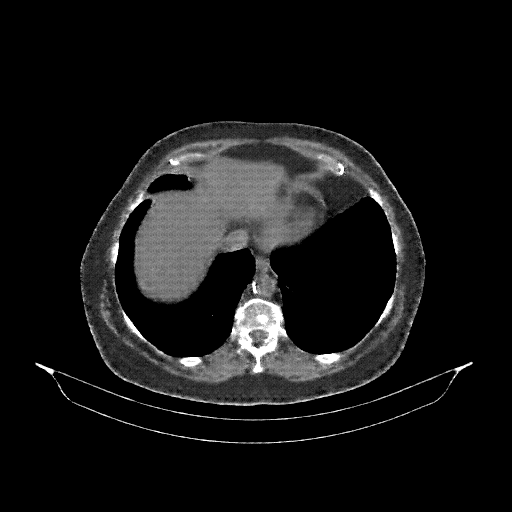

Generated VENOUS CT scan (A→B translation)

Lung window (WL -600, WW 1500 β†’ Low βˆ’1350, High +150)

Actual HU range: [-1160.8, 150.0]